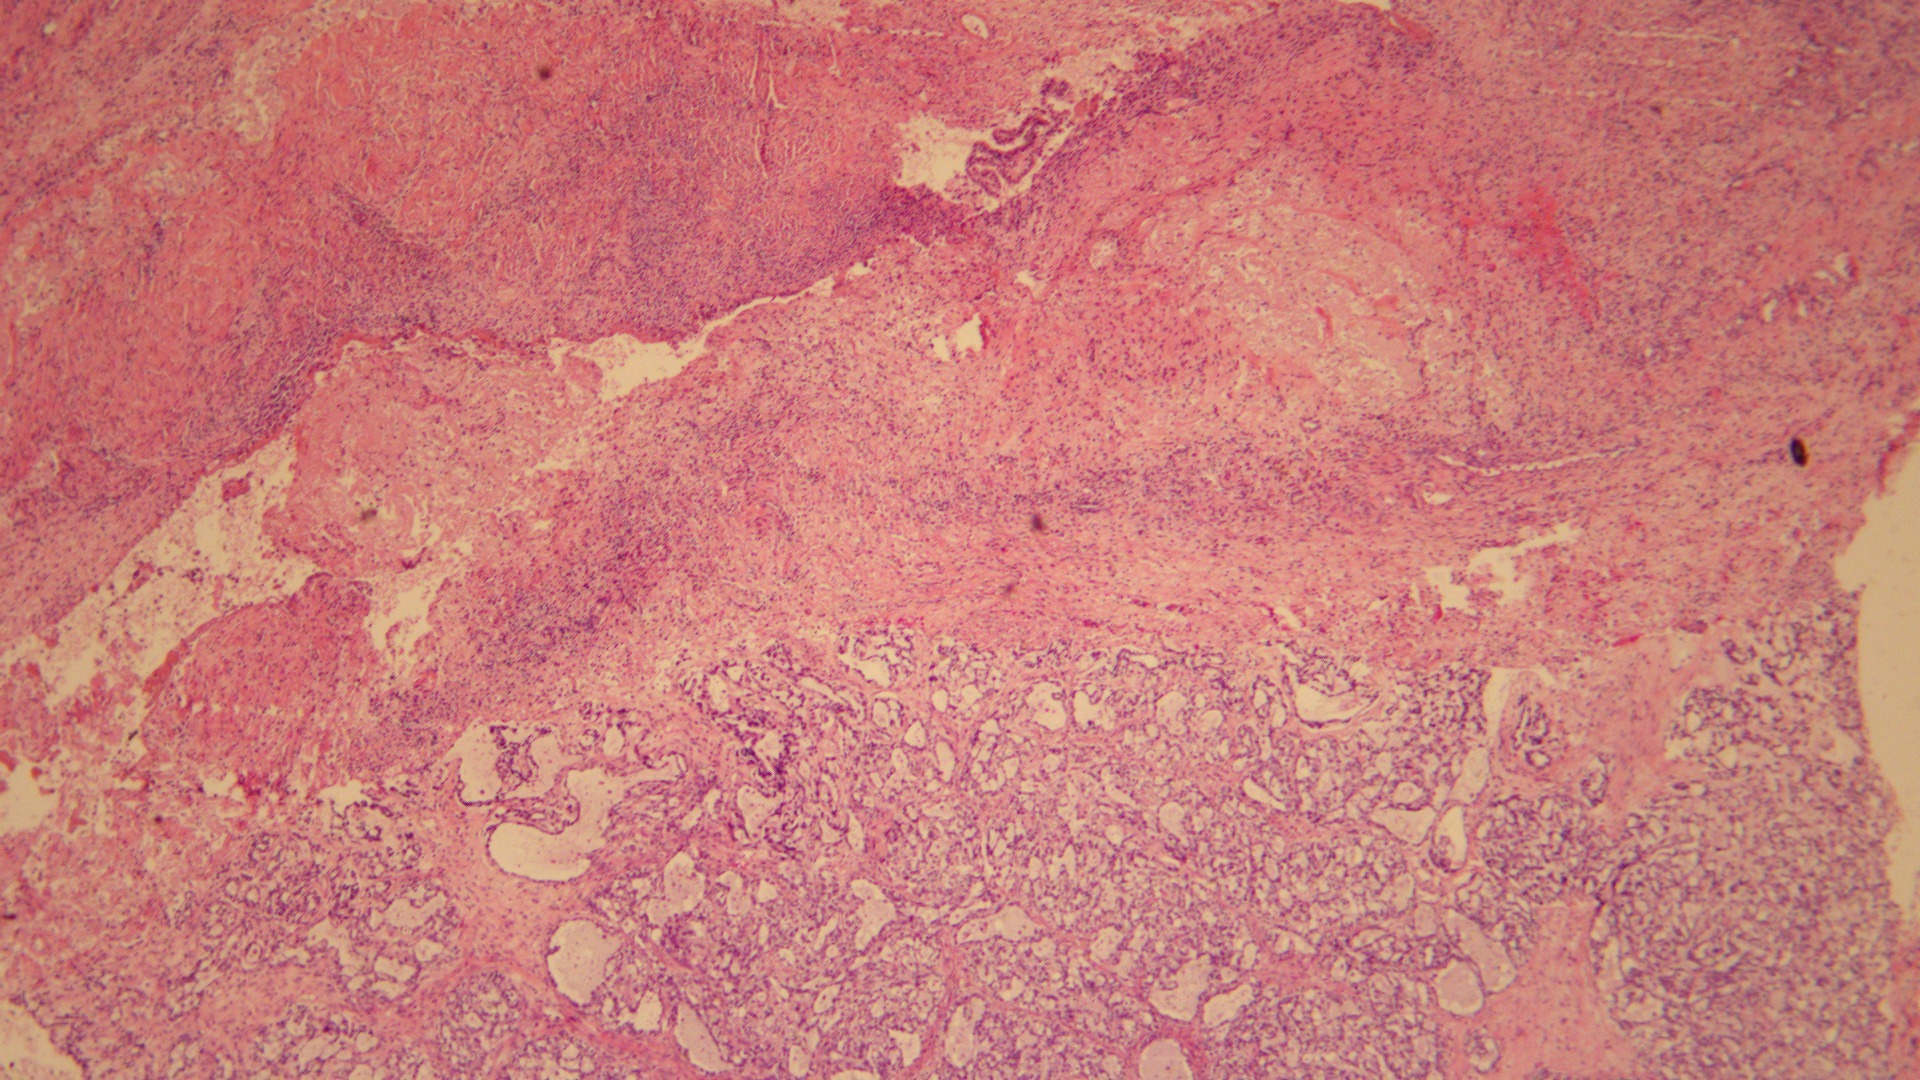

Among the 136 patients diagnosed with pure OCCC between 2010 and 2019, 83 (61%) were rendered as OCCC with endometriosis (Fig. 1), and 53 (39%) were assigned to OCCC without endometriosis (Fig. 2).

Fig. 1.

Fig. 1.Pure OCCC with endometriosis A typical OCCC arising from the

wall of an endometriotic cyst. Endometrial stroma and hemosiderin cells were

found in the ovarian sac wall (Hematoxylin and eosin stain; original

magnification,